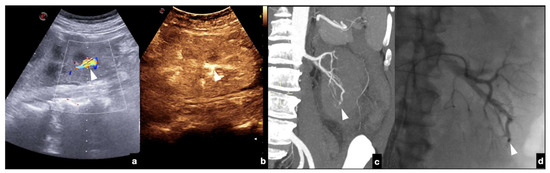

Follow-up CEUS of a 52−year-old blunt trauma patient with high-grade right kidney injury and extensive ischemia complication. Venous (a) phase CEUS examination shows multiple kidney lacerations with extensive ischemia complication and a small amount of perfused renal (caliper). At the same venous phase (b), CEUS active venous hemorrhage is well appreciated (arrow) confirmed at contrast-enhanced venous phase CT scan (c, arrow) and subsequent angiography (d).

Contained vascular injuries include pseudoaneurysms and arteriovenous fistulas. Pseudoaneurysms are focal outpouchings of the external vessel contour due to the partial disruption of the wall, which is contained by the tissue around the vessel (Figure 18, Figure 19 and Figure 20) [1,30].

High grade traumatic splenic injury with vascular complication. Arterial (a) and venous (b) phase CEUS examination in a 25−year-old patient admitted at the emergency department for blunt abdominal trauma, showing multiple splenic lacerations and a voluminous arteriovenous fistula (white arrowhead). Subsequent arterial (c) and portal vein (d) phase contrast-enhanced CT scan further confirmed the diagnosis (black arrowhead).

Arteriovenous fistulas consist of traumatic communication between the arterial and venous systems [1,30]. Fistulas are characterized as asymmetrical, early contrast opacification of a vein during the early arterial phase of the study (Figure 21).

Companion case of Figure 2b. Renal arteriovenous fistula (white arrowhead) at color–Doppler US (a) and CEUS (b), confirmed (c) at contrast-enhanced CT scan (arterial phase, coronal MIP reconstruction) and subsequent angiography (d).